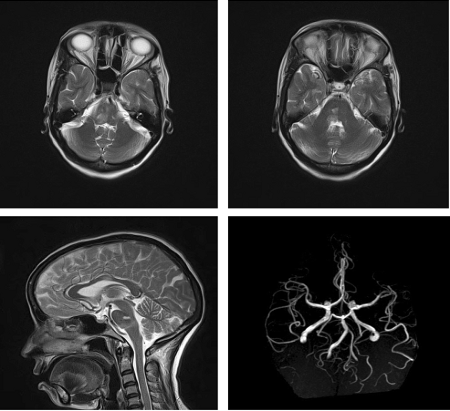

Adding to the list of named, numerical neuro-ophthalmological syndromes like one and half syndrome, this case report describes for the first time “Twenty and Half syndrome”, characterised by one and a half syndrome with bilateral seventh and right fifth nerve palsy (11 / 2 + 7 + 7 + 5 = 20½) in a patient with ischaemic stroke (Dube et al., 2019).